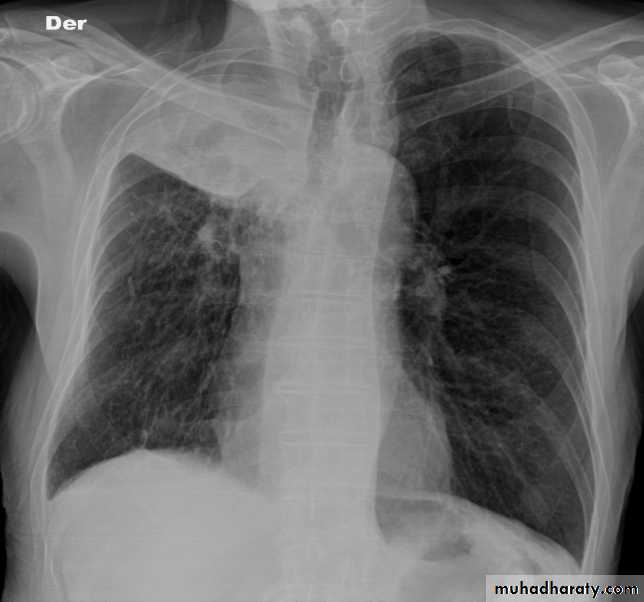

Lung abscess

CXR of adult male, PA and lateral views show:

Well defined rounded cavitatory lesion in the middle zone of the right lung with air fluid level insideLung abscess

Well defined rounded lesion in the middle zone of the right lung with air fluid level inside

Well defined rounded lesion in the upper zone of the right lung with air fluid level inside